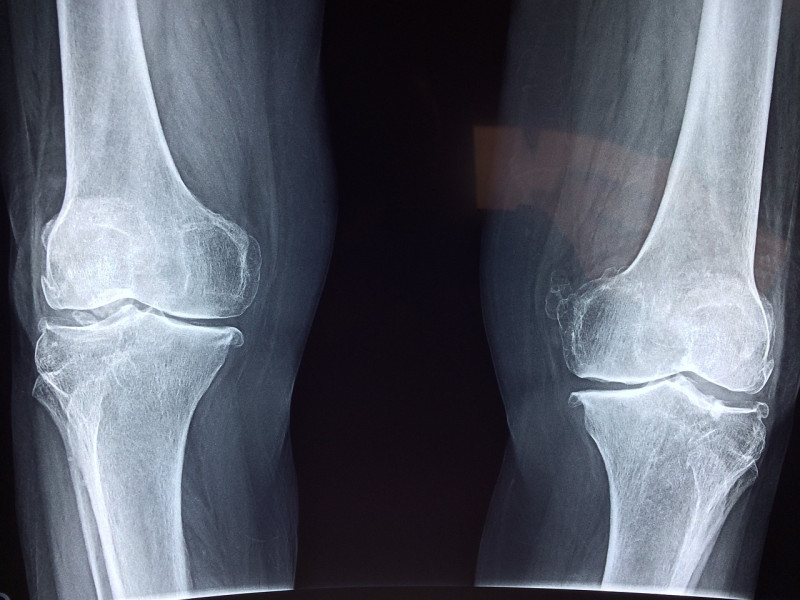

Joint replacement surgery is a transformative procedure that can alleviate pain and improve mobility for individuals suffering from severe joint conditions. Whether it’s a hip, knee, or shoulder replacement, the success of the surgery is often followed by a crucial phase: rehabilitation. Rehabilitation plays a pivotal role in restoring strength, flexibility, and functionality to the joint, ensuring a smooth transition back to an active and fulfilling life.